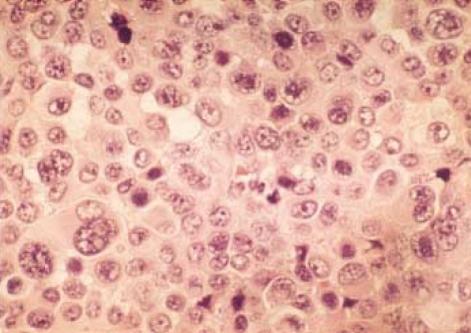

Malignant melanoma is the most common metastatic tumor of the gastrointestinal tract and can present with fairly common constitutional symptoms. A 36-yr-old woman was found to have a secondary malignant melanoma in the terminal ileum with profuse aneurysmal dilatation, which is not the typical presentation of the malignant melanoma in the small intestine. Radiologic studies revealed a large tumor involving the distal ileum with aneurysmal dilatations having afferent and efferent loops, which needed to be differentiated from malignant lymphoma and other gastrointestinal tumors. Exploratory laparotomy was done, and we found a huge mass with plentiful aneurysmal dilatations; much the same of the findings from the previous studies. Segmental resection with the surrounding omentum was done followed by end-to-end anastomosis between both ends of the remaining ileum. She had been free from any evidence of the local or systemic recurrence for one year after the completion of eighteen months of the subcutaneous interferon treatment; postoperatively however, the occurrence of metastatic mass at the right axilla rendered us from complete resection due to severe penetration into the vital nerves and vessels in the axilla.

恶性黑色素瘤是胃肠道最常见的转移性肿瘤,可表现出相当常见的全身症状。一名36岁女性被发现回肠末端有继发性恶性黑色素瘤,伴有大量动脉瘤样扩张,这并非小肠恶性黑色素瘤的典型表现。影像学研究显示,一个大肿瘤累及回肠远端,伴有动脉瘤样扩张,有输入袢和输出袢,需要与恶性淋巴瘤和其他胃肠道肿瘤相鉴别。进行了剖腹探查术,我们发现一个巨大肿块,有大量动脉瘤样扩张;与先前研究的发现大致相同。进行了包括周围网膜的节段性切除,然后对剩余回肠两端进行端端吻合。在完成18个月的皮下干扰素治疗后,她有一年没有任何局部或全身复发的迹象;然而,术后右腋窝出现转移性肿块,由于严重侵犯腋窝重要神经和血管,我们无法进行完全切除。